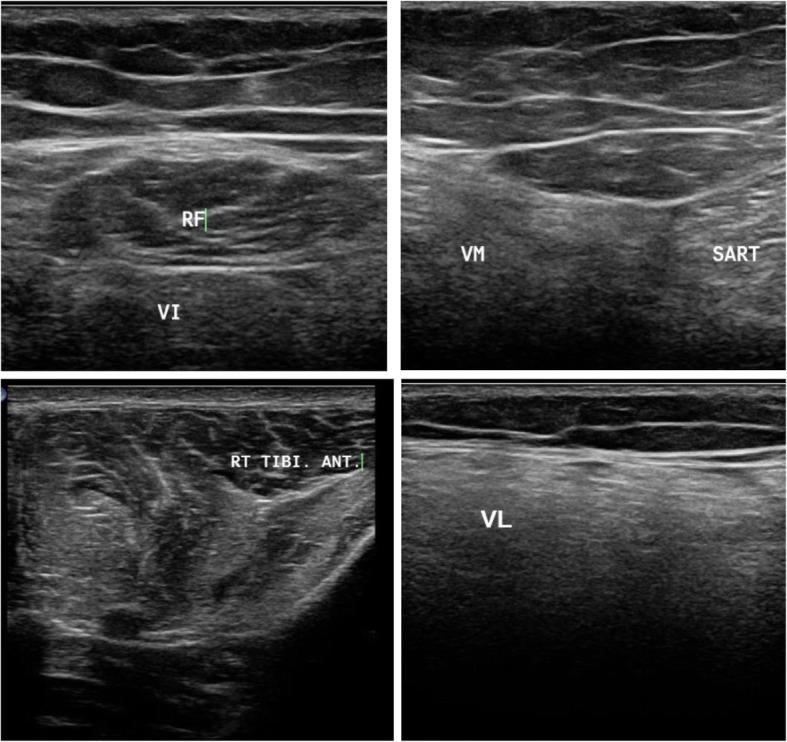

肌肉超声在辅助肌肉疾病临床诊断中的作用。

The role of muscle ultrasound in helping the clinical diagnosis of muscle diseases.

Selective involvement of certain muscles is an indicator for muscle diseases and helps to direct the diagnosis, but in some cases, it cannot be detected clinically; hence, the roles of muscle MRI and ultrasound are to detect this selectivity and facilitate the diagnosis.

The possibility of using muscle ultrasound as a screening tool when muscle diseases are suspected and as an alternative to MRI.

This cross-sectional descriptive study included 38 patients presented with clinical manifestations suggestive of muscle diseases. The patients were selected over a period of 1 year. All patients were subjected to thorough clinical assessment and muscle ultrasound of the thigh and leg for all patients, while 15 were subjected to MRI. Clinical and radiological assessments were performed separately, followed by both clinical and radiological findings to assess the power of combining the clinical and radiological assessments for the diagnosis of muscle diseases.

The clinical assessment reached a main provisional probable diagnosis in 53% cases, and radiological assessment blind to clinical data suggested diagnosis in 18 of the total cases, while the combination of both ultrasound and MRI could suggest diagnosis in 87% of the cases. The concordance ratio of ultrasound to MRI ranged between 78 and 100%.

The combination of clinical and radiological assessments of muscle diseases can suggest a main provisional probable diagnosis, especially when genetic diagnosis is not accessible, or to direct the genetic testing when it is available. Ultrasound can be used as a routine tool in screening and follow-up of muscle diseases.